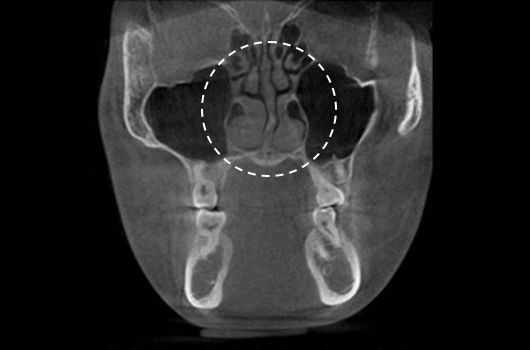

Operasi hidung CT 3D membantu pelaksanaan operasi hidung yang lebih canggih setelah menganalisis wajah secara cermat untuk menentukan mana yang terbaik.Analisis tiga dimensi digunakan untuk mengetahui keadaan secara umum, ukuran, bentuk, dan asimetri tulang hidung, tulang rawan septum hidung, dan jaringan kulit, yang tidak dapat ditentukan melalui konsultasi pada umumnya. Saat merencanakan revisi operasi hidung, kami dapat memeriksa elemen fungsional seperti deviasi septum hidung, bentuk implan yang ada, termasuk implan silikon, atau komplikasi dari operasi sebelumnya.

Pentingnya 3D-CT Scan pada Operasi Hidung

Dalam setiap konsultasi operasi hidung, Klinik Operasi Plastik Braun menggunakan 3D-CT scan untuk menganalisis isu-isu berikut dalam tiga dimensi: Rancangan bedah dapat dibuat lebih tepat dan potensi efek samping dapat berkurang dengan memahami lebih lanjut ukuran, bentuk, dan asimetri bagian hidung yang tak kasat mata dan struktur anatomi disekitarnya sebelum operasi.

1. Analisis tulang rawan septum dalam berbagai ukuran dan bentuk

2. Diagnosis dan tindakan untuk deviasi hidung dan deviasi septal

3. Analisis untuk lebar dan asimetri tulang hidung

4. Diagnosis Inferior turbinate asymametry dan pembedahan hidung tersumbat